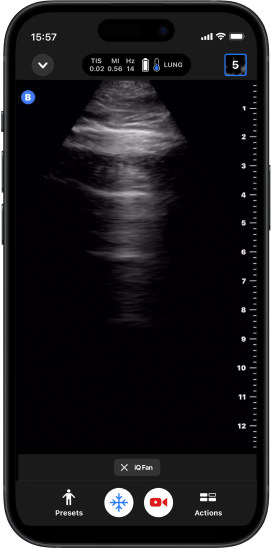

iQ Fan™

Esta ferramenta dedicada ao pulmão permite que você se beneficie da inclinação virtual para frente e para trás em tempo real, facilitando a visualização das linhas A.